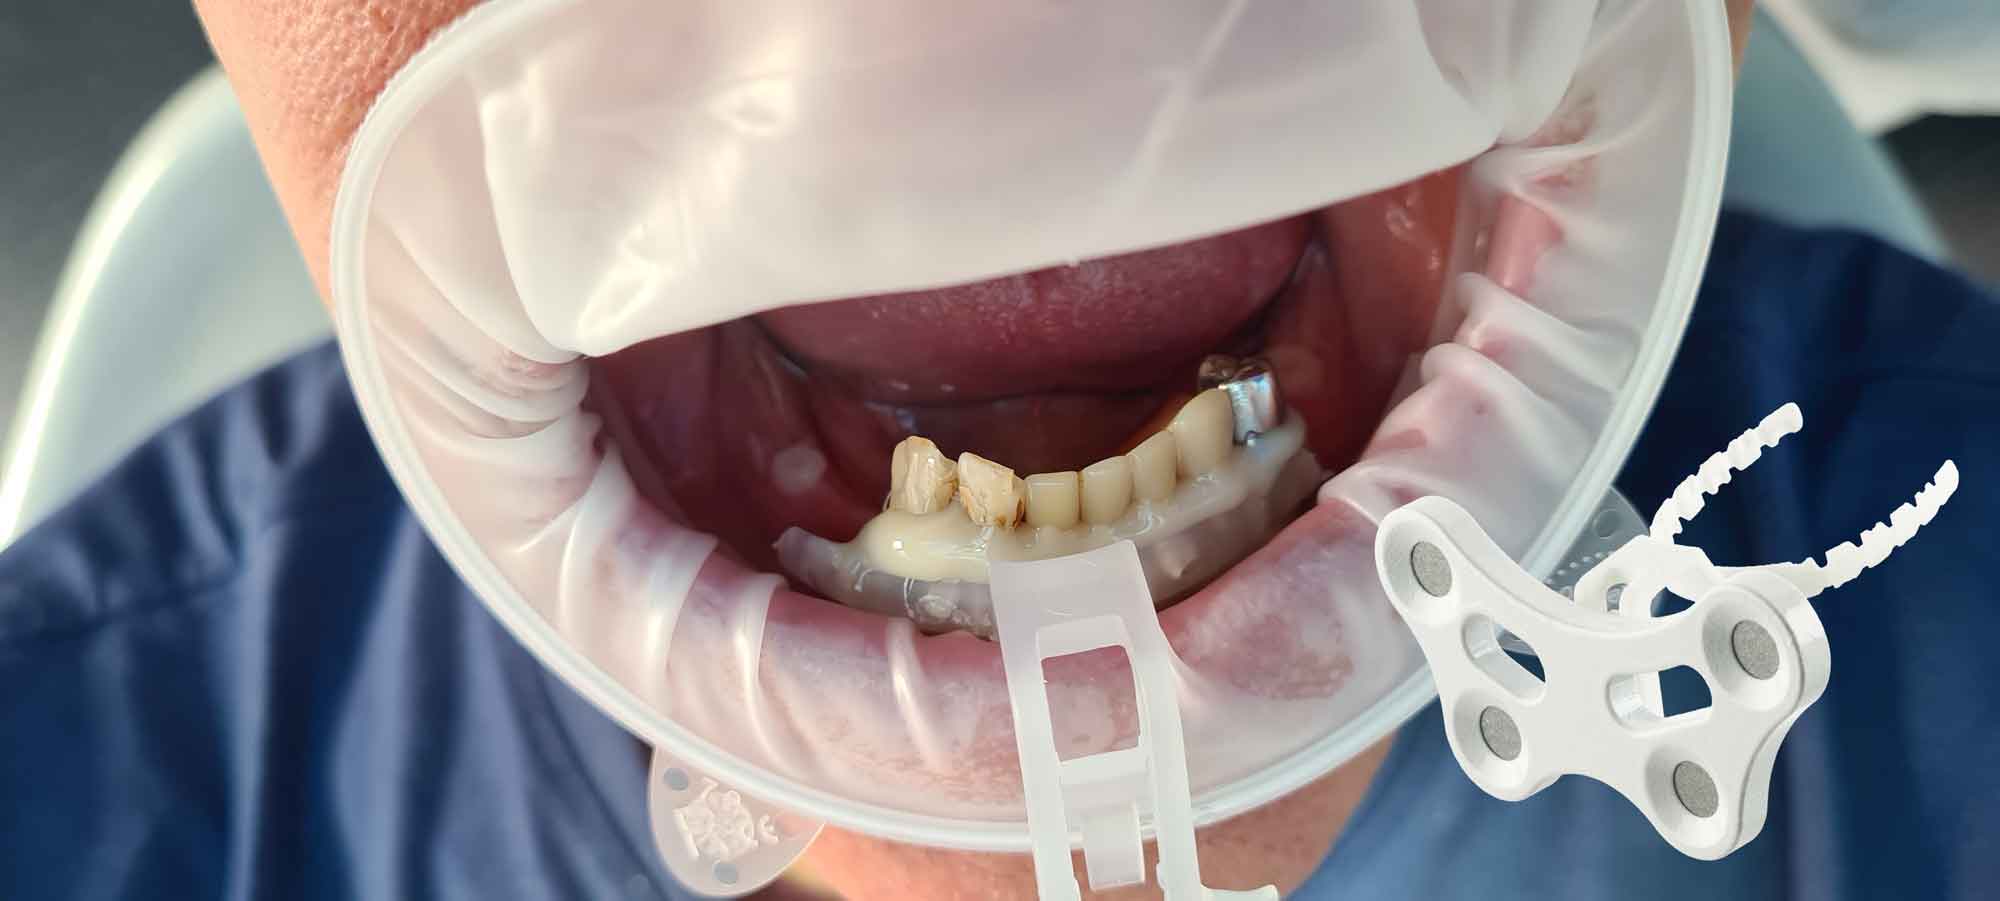

Before acquiring the CBCT, I added 2 pieces of composite to the mandible to be able to do the picking process during jaw motion recording. This is a useful trick to remember in a situation of lacking teeth.

Step 3 – MODJAW – Jaw motion registration

By importing patient DICOM files instead of the IOS scans, clinicians can register jaw motion, facilitating precise treatment planning.

Step 1

Import the segmented and converted CBCT models as initial models in TWIM

Step 2

Select 4 virtual points on the mandible of the imported bone mesh

Step 3

Fix the fork (paraocclusal clutch) to the mandible of the patient

Step 4

Pick the previously points in the patient's mouth using the Tally (stylus)